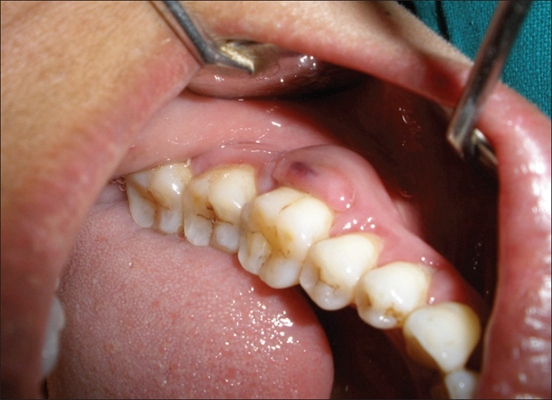

牙齦炎圖片

牙齦炎和牙周炎